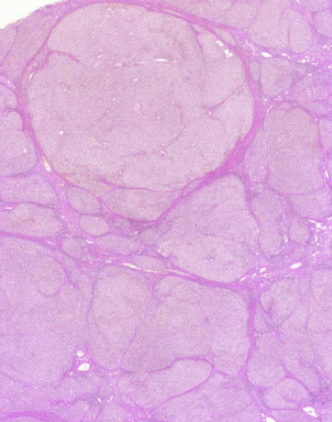

Kyhmystruuma

MIKÄ TAUTI? Kilpirauhanen muodostuu epäsäännöllisen muotoisista kyhmyistä. Follikkeliepiteeli on solu- ja tumarakenteeltaan säännöllistä. Follikkelit sisältävät kolloidia.